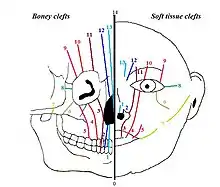

Tessier classification

In 1976 Paul Tessier published a classification on facial clefts based on the anatomical position of the clefts. The different types of Tessier clefts are numbered 0 to 14. These 15 different types of clefts can be put into 4 groups, based on their position:[4] midline clefts, paramedian clefts, orbital clefts and lateral clefts. The Tessier classification describes the clefts at soft tissue level as well as at bone level, because it appears that the soft tissue clefts can have a slightly different location on the face than the bony clefts.

Midline clefts

The midline clefts are Tessier number 0 ("median craniofacial dysplasia"), number 14 (frontonasal dysplasia), and number 30 ("lower midline facial cleft", also known as "median mandibular cleft"). These clefts bisect the face vertically through the midline. Tessier number 0 bisects the maxilla and the nose, Tessier number 14 comes between the nose and the frontal bone. The Tessier number 30 facial cleft is through the tongue, lower lip and mandible. The tongue may be absent, hypoplastic, bifid, or even duplicated.[5] People with this condition may be tongue-tied.[5]

Paramedian clefts

Tessier number 1, 2, 12 and 13 are the paramedian clefts. These clefts are quite similar to the midline clefts, but they are further away from the midline of the face. Tessier number 1 and 2 both come through the maxilla and the nose, in which Tessier number 2 is further from the midline (lateral) than number 1. Tessier number 12 is in extent of number 2, positioned between nose and frontal bone, while Tessier number 13 is in extent of number 1, also running between nose and forehead. Both 12 and 13 run between the midline and the orbit.

Orbital clefts

Tessier number 3, 4, 5, 9, 10 and 11 are orbital clefts. These clefts all have the involvement of the orbit. Tessier number 3, 4, and 5 are positioned through the maxilla and the orbital floor. Tessier number 9, 10 and 11 are positioned between the upper side of the orbit and the forehead or between the upper side of the orbit and the temple of the head. Like the other clefts, Tessier number 11 is in extent to number 3, number 10 is in extent to number 4 and number 9 is in extent to number 5.

Lateral clefts

The lateral clefts are the clefts which are positioned horizontally on the face. These are Tessier number 6, 7 and 8. Tessier number 6 runs from the orbit to the cheek bone. Tessier number 7 is positioned on the line between the corner of the mouth and the ear. A possible lateral cleft comes from the corner of the mouth towards the ear, which gives the impression that the mouth is bigger. It’s also possible that the cleft begins at the ear and runs towards the mouth. Tessier number 8 runs from the outer corner of the eye towards the ear. The combination of a Tessier number 6-7-8 is seen in the Treacher Collins syndrome. Tessier number 7 is more related to hemifacial microsomia and number 8 is more related to Goldenhar syndrome.